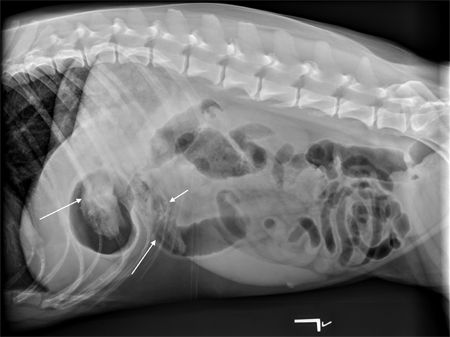

Also, things are hidden on the down side that you can't usually see until you flip the patient over to allow gas in the region to provide radiographic contrast with the soft tissue and fluid that may be present, especially in the abdomen. For example, in most dogs linear foreign bodies get caught in the pylorus of the stomach. A right lateral radiograph puts that side down so it's surrounded by fluid. Therefore the soft tissue of the foreign body blends with the fluid in the stomach and you can't see the lesion. If you're worried about a linear foreign body, take a left lateral radiograph to put gas in the pylorus, allowing you to see the foreign body (Figure 1).

Figure 1A: This left lateral radiograph shows a foreign body (sock) within the pylorus of the stomach and the descending duodenum. Note that you can barely see the linear striations of the lesion on the right lateral radiograph (Figure 1B), but it is clearly seen on the left lateral when gas is present in the fundus. (Radiography images courtesy of Dr. Anthony Pease.)

Figure 1B: Right lateral view.